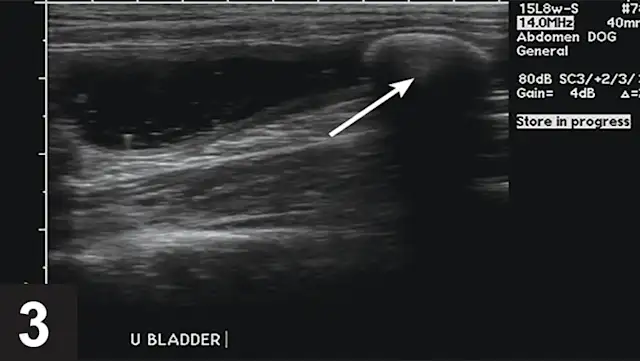

Urate uroliths most commonly form in younger dogs (mean age, 3–4 years) and are usually small, smooth, round or ovoid, and green or brown (Figure 2). They are relatively radiolucent and may require ultrasonography or contrast radiography to be observed (Figures 3–6). Urinary tract infections (UTIs), especially those with urease-producing bacteria, may facilitate ammonium acid urate crystallization. UTI may also occur secondary to urolith-induced mucosal damage and altered local host defense mechanisms. High dietary protein usually increases the urinary excretion of both UA and ammonium ions in affected dogs. Ammonia, produced by renal tubular cells from glutamine, diffuses into the tubular lumen and serves as a buffer for secreted hydrogen ions, thereby forming ammonium ions. Ammonium ions are relatively lipid insoluble and become trapped within the tubular fluid. Acidic urine decreases the solubility of uric acid. AU crystals are usually yellow–brown and spherical with multiple irregular protrusions and are often referred to as thorn apple crystals (Figures 7 & 8).

Monitoring dogs at risk for AU urolith recurrence should include close monitoring for signs of lower urinary tract inflammation or urethral obstruction, as well as periodic evaluation of urine pH and urine sediment for crystalluria. Any UTIs should be treated on the basis of urine culture and sensitivity testing. Recurrence of AU uroliths can be confirmed with imaging which may require ultrasonography or contrast radiography.